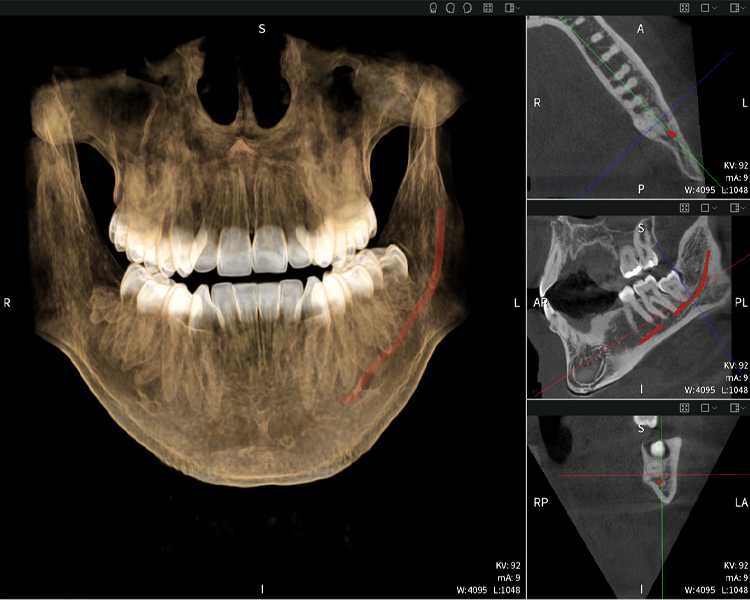

Nachstehend finden Sie einen Fall von Dr. med. dent. Oliver A. Centrella, in dem die CBCT-Aufnahmen mit Seethrough Max entscheidende Informationen zur komplexen Anatomie sowie zur kritischen Beziehung zwischen den Weisheitszähnen und dem Nervus alveolaris inferior lieferten. Bei diesem Fall besteht eine Indikation zur chirurgischen Entfernung der Weisheitszähne.

Abbildungen b–d zeigen verschiedene Ansichten einer 3D-Rekonstruktion des Unterkiefers und bieten eine umfassende Übersicht über die Anatomie des Unterkiefers, die Lage der Nerven im Verhältnis zu den Zähnen und ermöglichen die Beurteilung der Zahnsymmetrie und Ausrichtung.

Abbildung d zeigt den bereits vorbehandelten Zahn 48, dessen Krone entfernt wurde und dessen Wurzeln nahe am Nerv belassen wurden, was das hohe Risiko einer Nervenschädigung verdeutlicht.